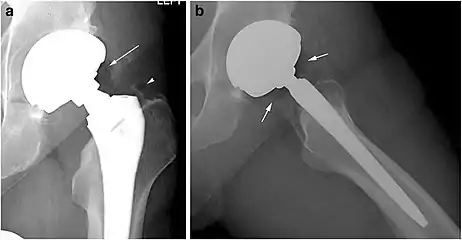

- X-ray of a hip with hip replacement and pneumarthrosis, in this case aseptic.